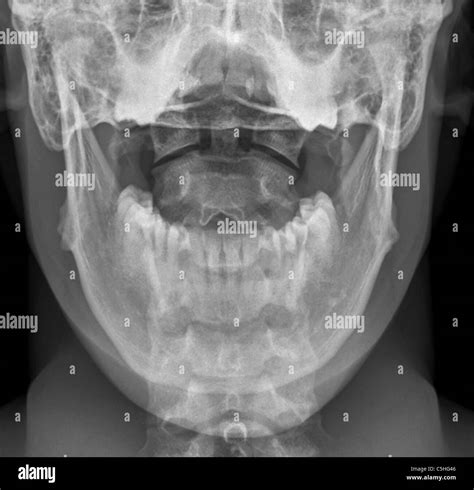

Receiving medical imaging results can often feel overwhelming, especially when you are unsure what the terminology implies for your long-term health. A normal neck X-ray, medically referred to as a cervical spine radiograph, is a common diagnostic tool used by healthcare providers to visualize the seven vertebrae that make up your neck. If your report indicates that your findings are within normal limits, it typically means the radiologist did not detect any fractures, significant misalignment, or severe degenerative changes at the time of the scan. Understanding what this diagnostic baseline represents is crucial for anyone navigating neck pain, stiffness, or post-injury evaluation.

The human neck is a complex structure consisting of seven vertebrae (C1 through C7), discs, muscles, ligaments, and nerves. A normal neck X-ray focuses primarily on the bony structures. Because X-rays are excellent at capturing high-density tissues, they provide a clear view of the vertebrae, the spaces between them (which house the discs), and the alignment of the spine.

Interpreting Your Radiologist Report

When you look at your results, you may encounter medical jargon that can be confusing. A report stating "no acute osseous abnormality" is the clinical way of describing a normal neck X-ray regarding fractures. The following table helps break down common terms found in these reports.